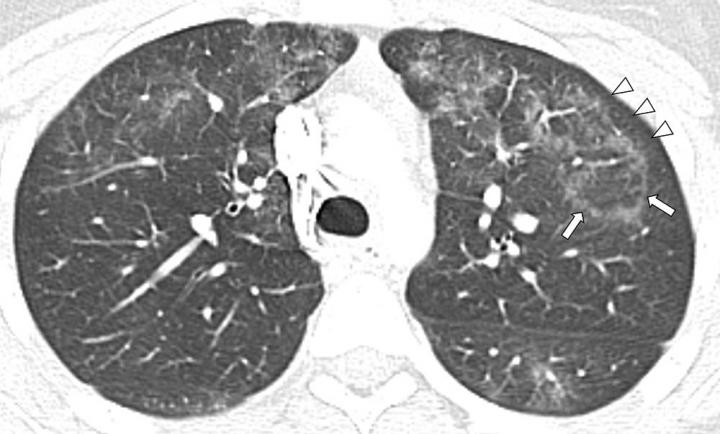

image: Image in a 16-year-old girl with history of chronic abdominal pain and electronic cigarette product use with nicotine and tetrahydrocannabinol for 1 year who presented with acute abdominal pain and vomiting 1 day prior to admission. Patient later developed shortness of breath and increased work of breathing. Axial lung window (width, 1500; level, ?700) image of chest CT with contrast enhancement performed 1 day prior to admission shows presence of central ground-glass opacity surrounded by denser complete ring of consolidation, also known as the reversed halo sign (atoll sign) (arrows). Subpleural sparing (arrowheads) of lung abnormality is also seen.

The results showed characteristic chest X-ray and CT findings. Bilateral and symmetric ground-glass opacity in the lungs, frequently associated with consolidation, often of lower lobe predominance, was the key imaging finding. On CT, subpleural sparing was also visualized in 79% of patients.

"Another imaging feature observed on CT in 36% of our pediatric patients with EVALI, was the reversed halo sign, which is characterized by the presence of a central ground-glass opacity surrounded by denser consolidation of crescentic shape or complete ring," Dr. Artunduaga said.